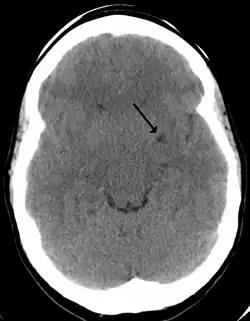

Perivascular spaces are most commonly located in the basal ganglia and white matter of the cerebrum, and along the optic tract.[13] The ideal method used to visualize perivascular spaces is T2-weighted MRI. The MR images of other neurological disorders can be similar to those of the dilated spaces. These disorders are:[7]

Perivascular spaces are distinguished on an MRI by several key features. The spaces appear as distinct round or oval entities with a signal intensity visually equivalent to that of cerebrospinal fluid in the subarachnoid space.[7][14][15] In addition, a perivascular space has no mass effect and is located along the blood vessel around which it forms.[14]